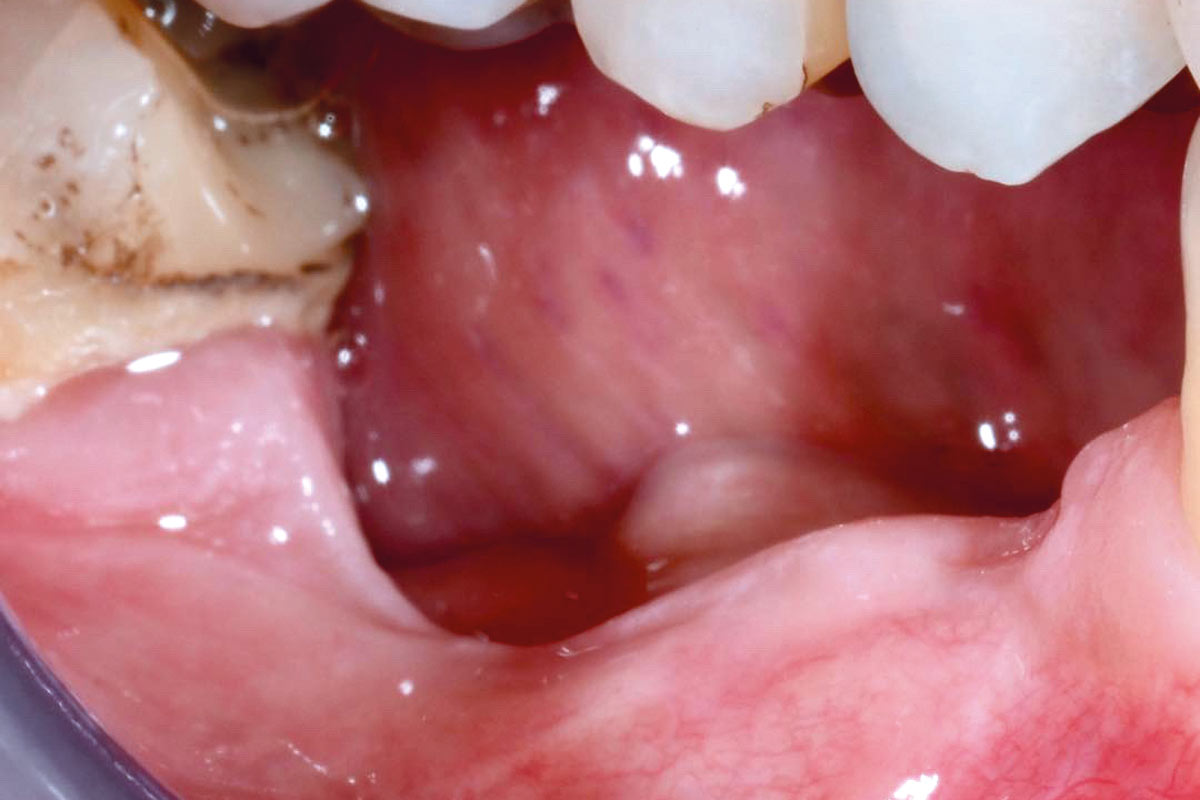

10/29 - Dehiscence of permamem® 3 months post-operatively. No signs of infection, the patient did not report painVertical bone augmentation and broadening of attached gingiva using cerabone®, permamem® and mucoderm® - Dr. R. Naimoli